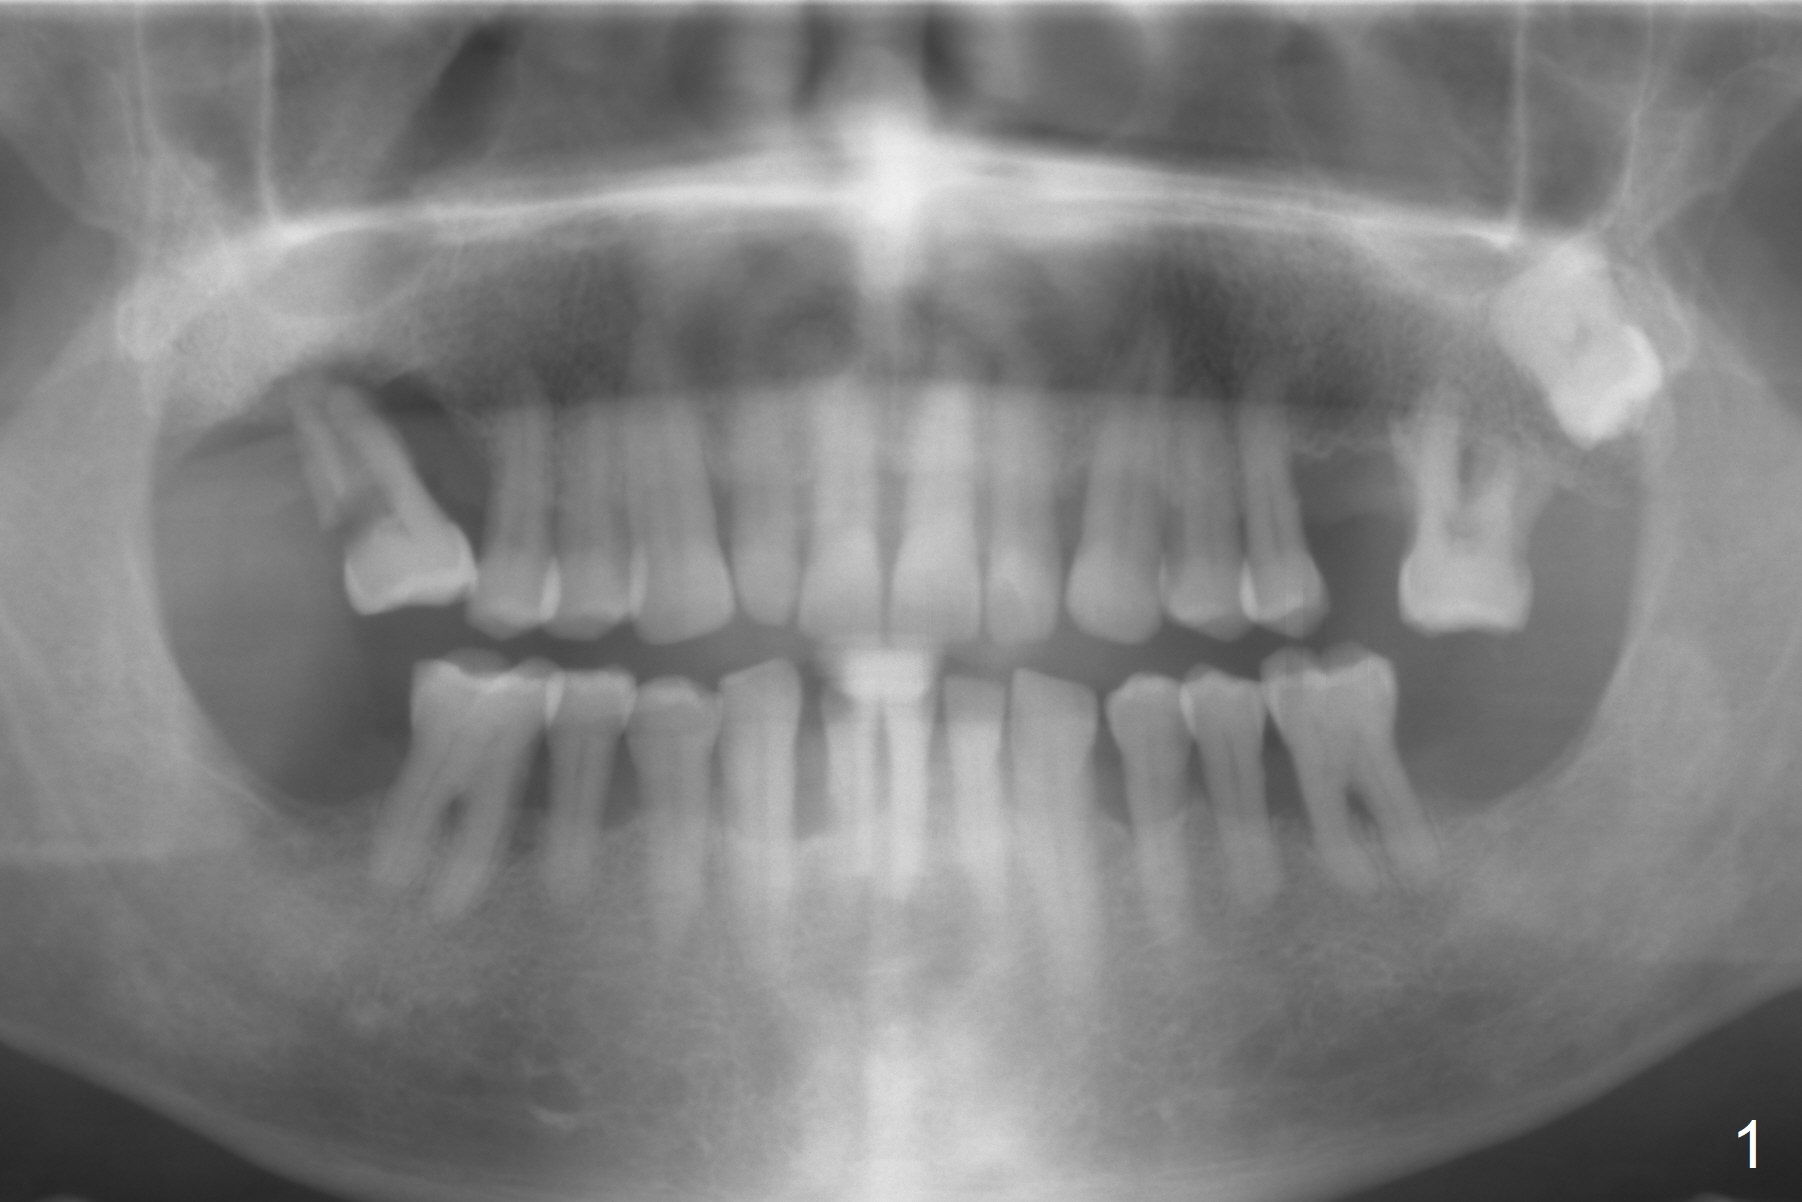

A 53-year-old man has severe peridontitis (Fig.1).  The tooth #3 has exfoliated.  The 1st implant will be placed at #3, where the gingiva seems to be thick (Fig.2: 10 mm).  A mill abutment will be used.